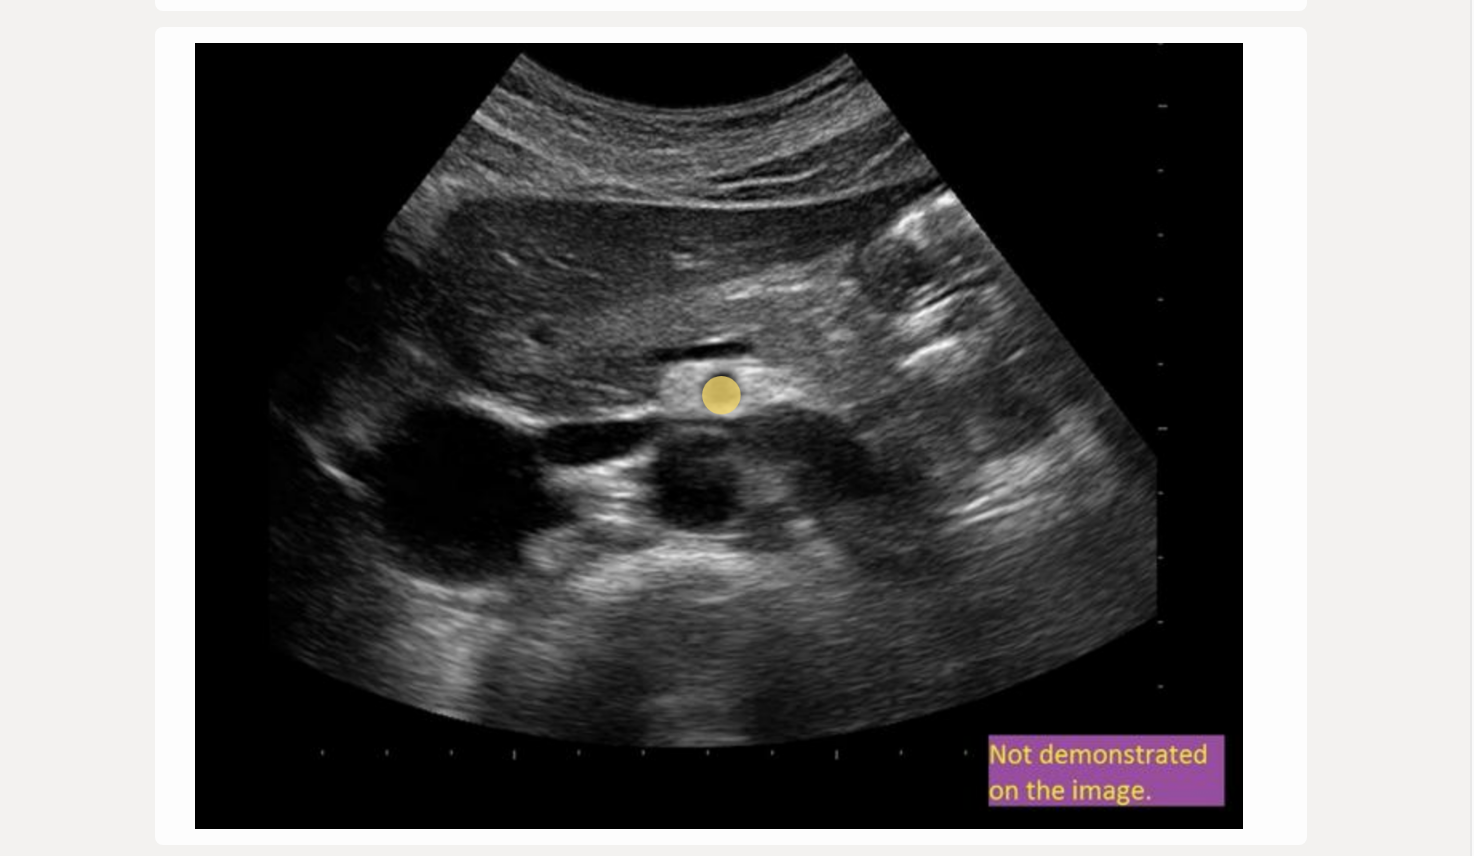

![<p>find the left renal vein</p><p>.</p><p>[left renal vein = between SMA + AO]</p>](https://knowt-user-attachments.s3.amazonaws.com/522e32e3-0c34-4507-81e5-c8f625b0171c.png)

find the left renal vein

.

[left renal vein = between SMA + AO]

left renal vein = between SMA + AO